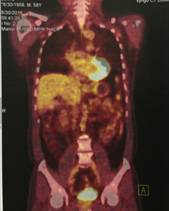

v Bệnh nhân được đánh giá đáp ứng hoàn toàn, tiếp tục theo dõi và khám định kỳ. Hiện tại sau điều trị 6 năm bệnh nhân ổn định. Hình ảnh PET/CT không thấy tăng hấp thu FDG bất thường tại cơ quan bộ phận nào khác của cơ thể.

Hình 3: Hình ảnh PET/CT sau điều trị 6 năm không thấy tăng hấp thu FDG bất thường tại cơ quan bộ phận nào khác của cơ thể.

Hình 6: Sau điều trị 6 năm: hình ảnh chụp PET/CT sau điều trị cho thấy khối hạch cổ trái tan biến hoàn toàn, không thấy tăng hấp thu FDG tại cơ quan bộ phận khác của cơ thể.